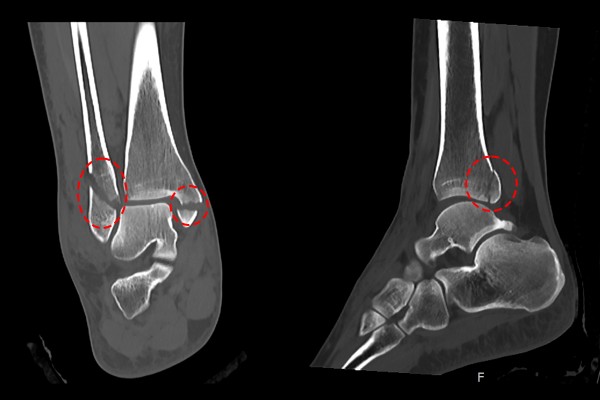

육안으로 보았을 때 발목이 많이 부어 있었고, 지참하신 X-RAY 사진을 보았을 때 안쪽 복숭아뼈(내복사), 바깥쪽 복숭아뼈(외복사)에 골절이 확인되었습니다.

더욱 자세한 확인을 위해, CT 영상을 확인해보니 내/외복사 골절과 함께 뒤쪽 복숭아뼈(후복사)골절까지 확인되며 발목 삼복사 골절(Fx. trimalleolar ankle Rt)을 진단하였습니다.